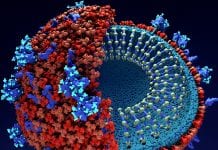

Exploring vaccine storage and delivery

HEQ speaks with Thomas Sorensen, Senior Manager at UNICEF, about the cold chain and the challenges facing vaccine refrigeration.

Global charity UNICEF has been delivering...

Refrigeration and the vaccine cold chain

HEQ speaks with AREA President Marco Buoni about the role of refrigeration and the cold chain in combating the COVID-19 pandemic.

The cold chain is...